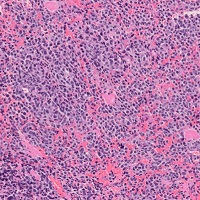

ユーイング肉腫